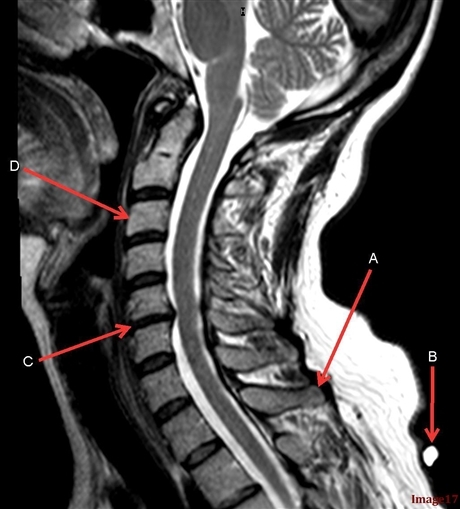

: Image 17 was acquired in the _______ imaging plane.

Sagittal